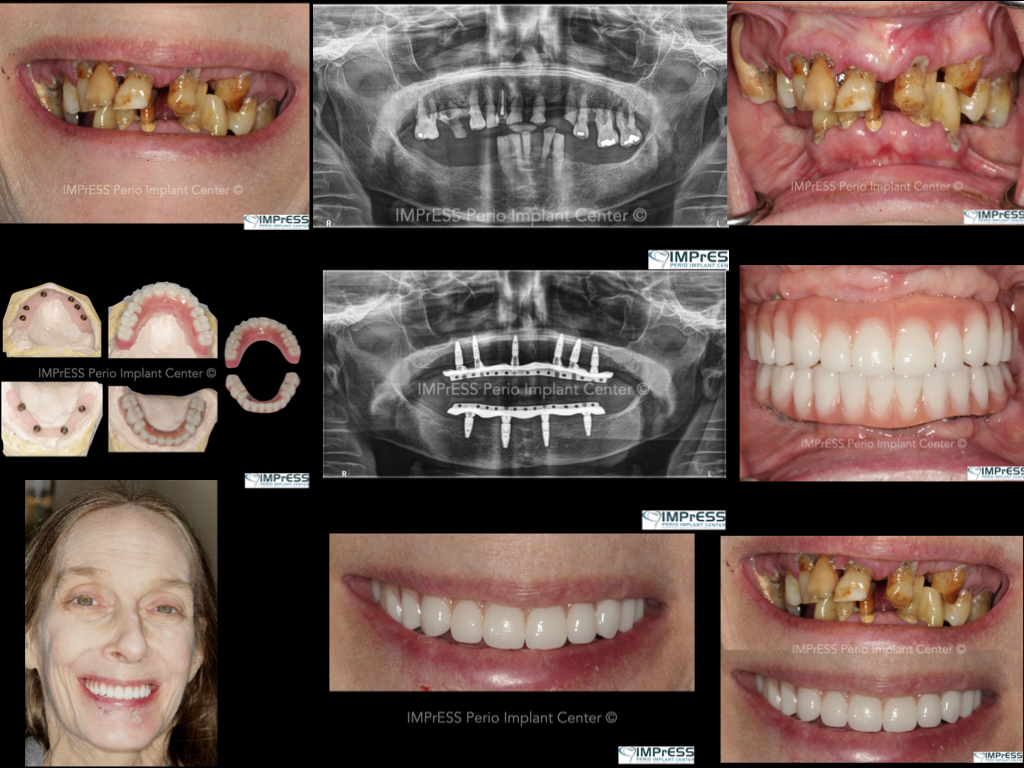

Before & Afters of Dental Implant Patients

Complete Dental Implant Cases Gallery

General Disclaimer: The results in the photographs are examples only and do not imply any certainty of the result of a procedure, and all outcomes are subject to the circumstances of the individual patient.